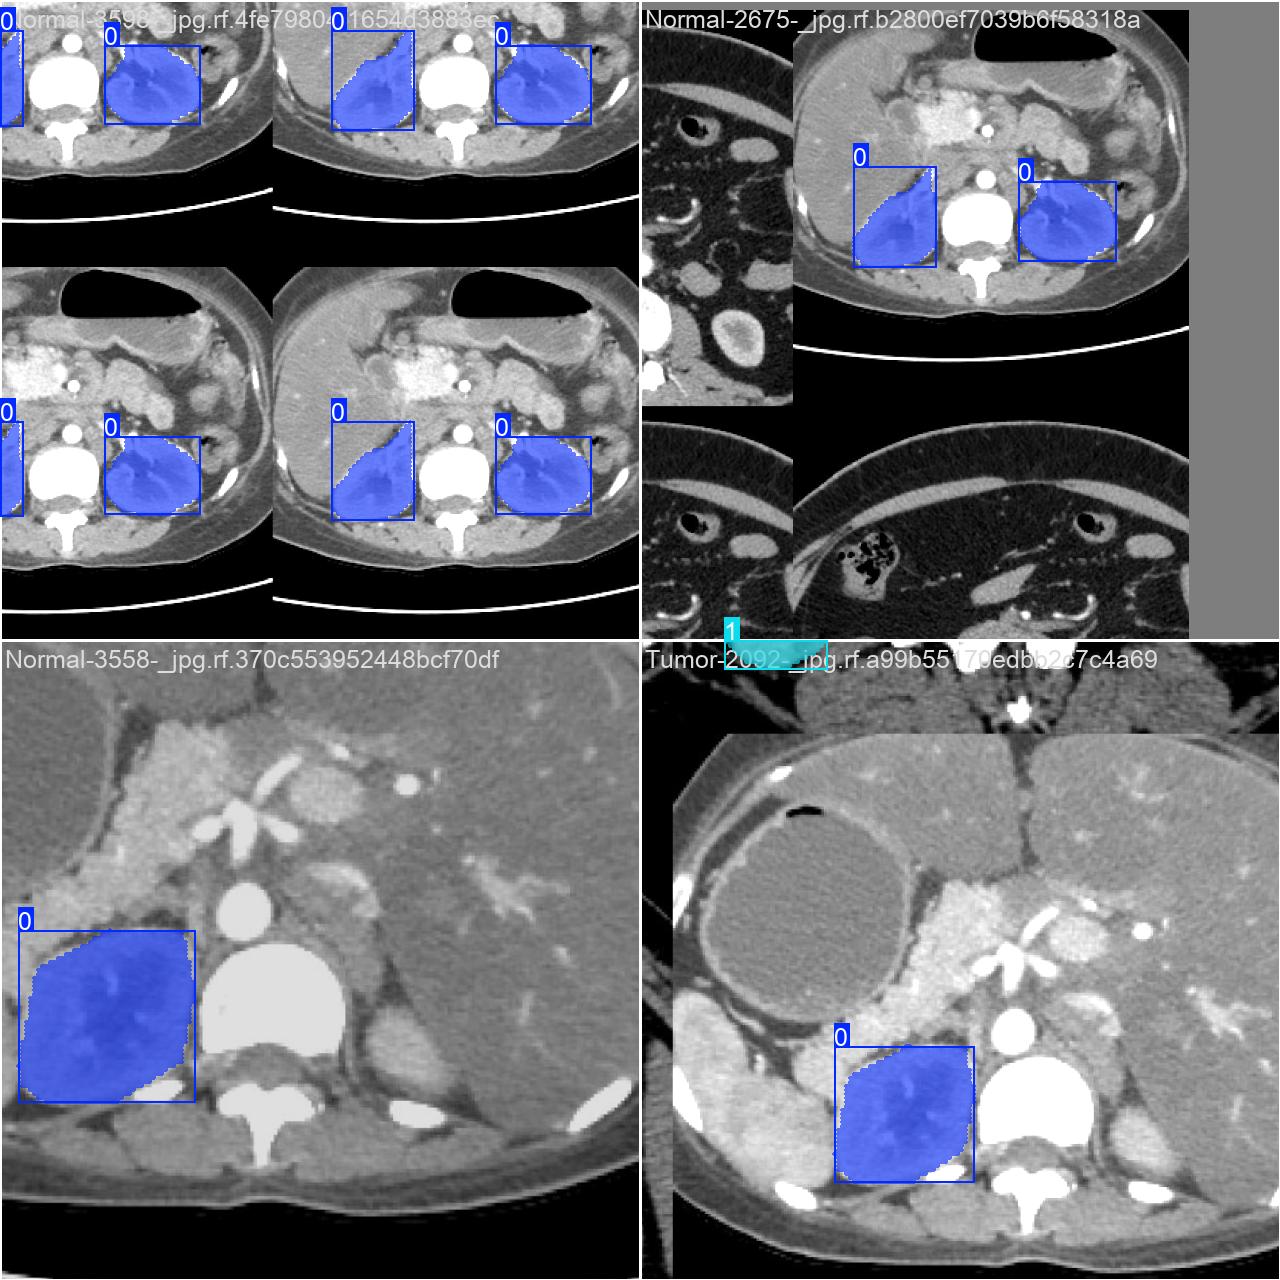

部分数据集图像如下图所示:

部分标注如下图所示:

这种数据分布方式保证了数据在模型训练、验证阶段的均衡性,为 YOLOv8n 模型的开发与性能评估奠定了坚实基础。